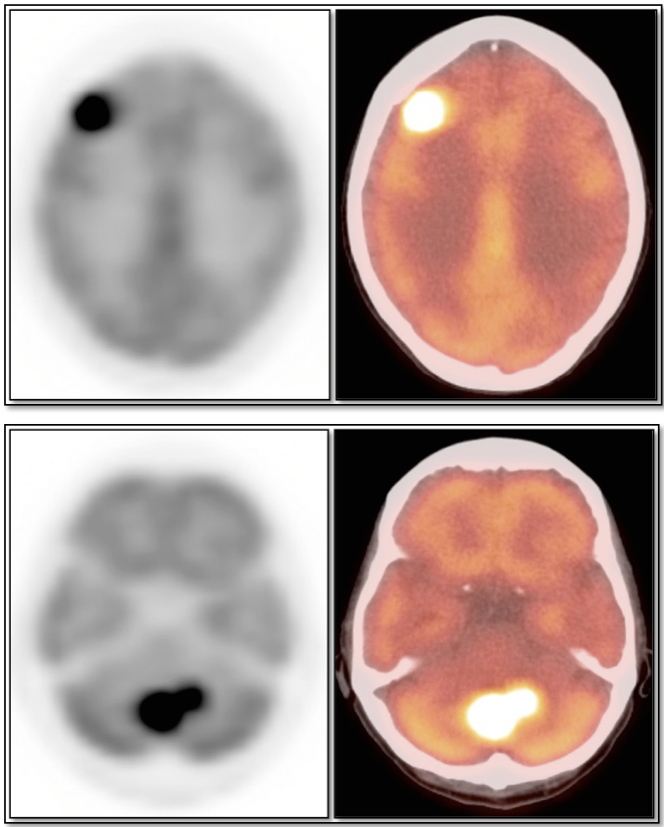

PET/CT is generally not used to decide whether or not a patient has a primary brain tumor (a diagnosis of brain tumor has nearly always already been made by CT or MRI prior to PET/CT scanning). The true value of PET/CT is determining whether or not a known tumor is “high-grade” or not.

- Characterizing lesions as “low-grade” or “high-grade” (with dramatic implications on management & prognosis):

- Low-Grade: Uptake ≈ white matter (may use contralateral centrum semiovale for comparison)

- High-Grade: Uptake > white matter (≈ grey matter)

- As the brain lesion may not clearly identifiable on the non-contrast CT images, it is essential to view the prior MRI (or CT) that lead to the initial diagnosis of “brain tumor”.

- Differentiate radiation necrosis (or chemonecrosis) from active malignancy.

Radiation Necrosis (or Chemonecrosis):

- Necrosis presents months to years after radiation therapy (rarely < 3 months post radiation).

- Difficult to differentiate necrosis from malignancy on MRI, as both demonstrate enhancement.

- Necrosis is typically non-avid on PET images.

- Recurrent malignancy will demonstrate FDG uptake, often focal and involving only a small portion of a surgical cavity. The uptake may be intense (an easy diagnosis) or may be minimally above adjacent background uptake (a more difficult diagnosis, which may require follow-up).

- FDG-avid recurrence should correspond to the area of enhancement noted on MRI (MRI should be done first, with images available at time of PET/CT interpretation).

- If no evidence of pathologic uptake, we report, “There is no evidence of high-grade tumor recurrence.”

Brain Metastases:

- Far more common than primary lesions (> 10 times).

- If small and at grey-white junction, can be easily overlooked.

- Commonly from lung, breast, melanoma and GI primaries.

CNS Lymphoma:

- Usually very hypermetabolic (FDG uptake is often greater than high-grade gliomas or metastatic lesions).